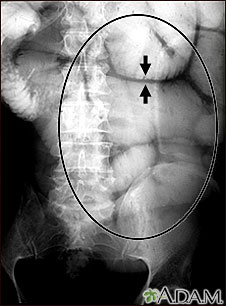

Ileus - x-ray of bowel distension

Ileus - x-ray of bowel distension

This abdominal x-ray shows thickening of the bowel wall and swelling (distention) caused by a blockage (pseudo-obstruction) in the intestines. A solution containing a dye (barium), which is visible on X-ray, was swallowed by the patient (the procedure is known as an upper GI series).